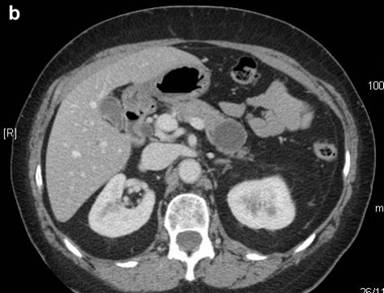

Then, abdominal computed tomography (CT) performed six months later showed that the cystic lesion did not increase in size, but had a 12.0 mm lamellar calcification on the posterior wall and impressed the left renal vein, without any signs of invasion of the surrounding tissues (Figure 1bc). The cystic lesion had no increased tracer uptake at 18F-FDG-positron emission tomography (PET). The patient had no symptoms related to the pancreatic lesion and blood tests were all normal. Serum carbohydrate antigen 19-9 (CA 19-9) and carcinoembryonic antigen (CEA) levels were normal.

Figure 1. a. The pancreatic tail cyst at MRI scan. b. c. CT scan showing a 4 cm cystic fluid mass arising from the tail of the pancreas, with well defined margins and a lamellar calcification on the posterior wall. |